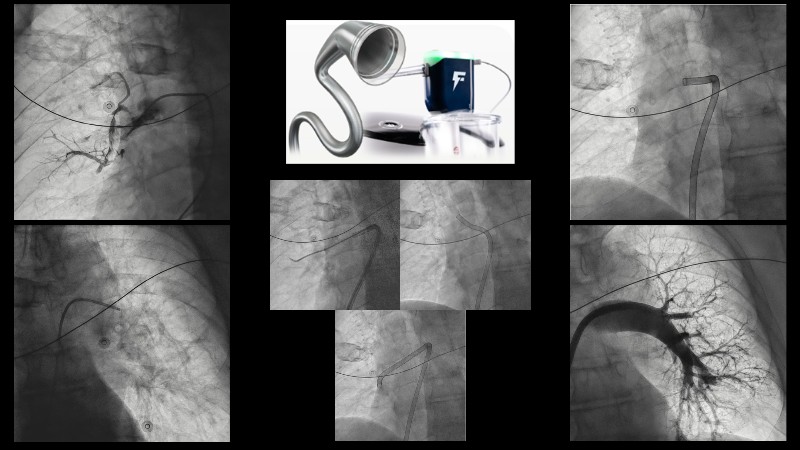

Watch this EuroPCR 2025 session on pulmonary embolism to explore the role of computer-assisted vacuum thrombectomy (CAVT) as an alternative to medical treatment in high-risk (massive) PE, supported by insights from the STRIKE PE study. Discover how CAVT rapidly and effectively offloads the right ventricle in intermediate-high-risk PE patients, especially those with a high bleeding risk. Review safety and efficacy data from a cohort of 450 patients demonstrating consistent procedural success. In short, this video provides a clear understanding of key procedural considerations, the latest evidence on Penumbra technology, and how ongoing innovation is shaping the future of PE management.

- To understand main procedural factors in pulmonary embolism treatment

- To learn latest published data on Penumbra technology

- To discuss how technological innovation can improve the procedure